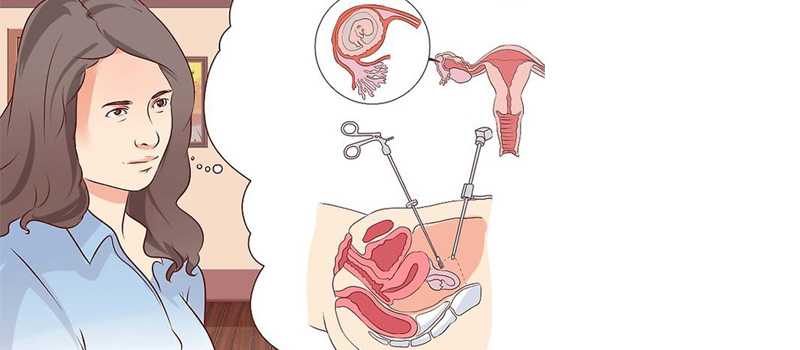

An ectopic pregnancy occurs when the fertilized egg attaches itself in a place other than inside the uterus. The fallopian tubes are not designed to hold a growing embryo; thus, the fertilized egg in a tubal pregnancy cannot develop properly and must be treated. An ectopic pregnancy happens in 1 out of 50 pregnancies.

Unfortunately, the baby cannot be saved in an ectopic pregnancy. Treatment is usually needed to remove the pregnancy before it grows too large.

The main treatment options are:

• expectant management – your condition is carefully monitored to see whether treatment is necessary

• medication – a medicine called methotrexate is used to stop the pregnancy growing

• surgery – surgery is used to remove the pregnancy, usually along with the affected fallopian tube

In most cases, keyhole surgery (laparoscopy) will be carried out to remove the pregnancy before it becomes too large.

During a laparoscopy:

• you're given general anaesthetic, so you're asleep while it's carried out

• small cuts (incisions) are made in your tummy

• a thin viewing tube (laparoscope) and small surgical instruments are inserted through the incisions

• the entire fallopian tube containing the pregnancy is removed if your other fallopian tube looks healthy – otherwise, removing the pregnancy without removing the whole tube may be attempted (salphingostomy)

Removing the affected fallopian tube is the most effective treatment and isn't thought to reduce your chances of becoming pregnant again.

Your doctor will discuss this with you beforehand, and you'll be asked whether you consent to having the tube removed.

Most women can leave hospital a few days after surgery, although it can take 4 to 6 weeks to fully recover.

If your fallopian tube has already ruptured, you'll need emergency surgery.

The surgeon will make a larger incision in your tummy (laparotomy) to stop the bleeding and repair your fallopian tube, if that's possible.